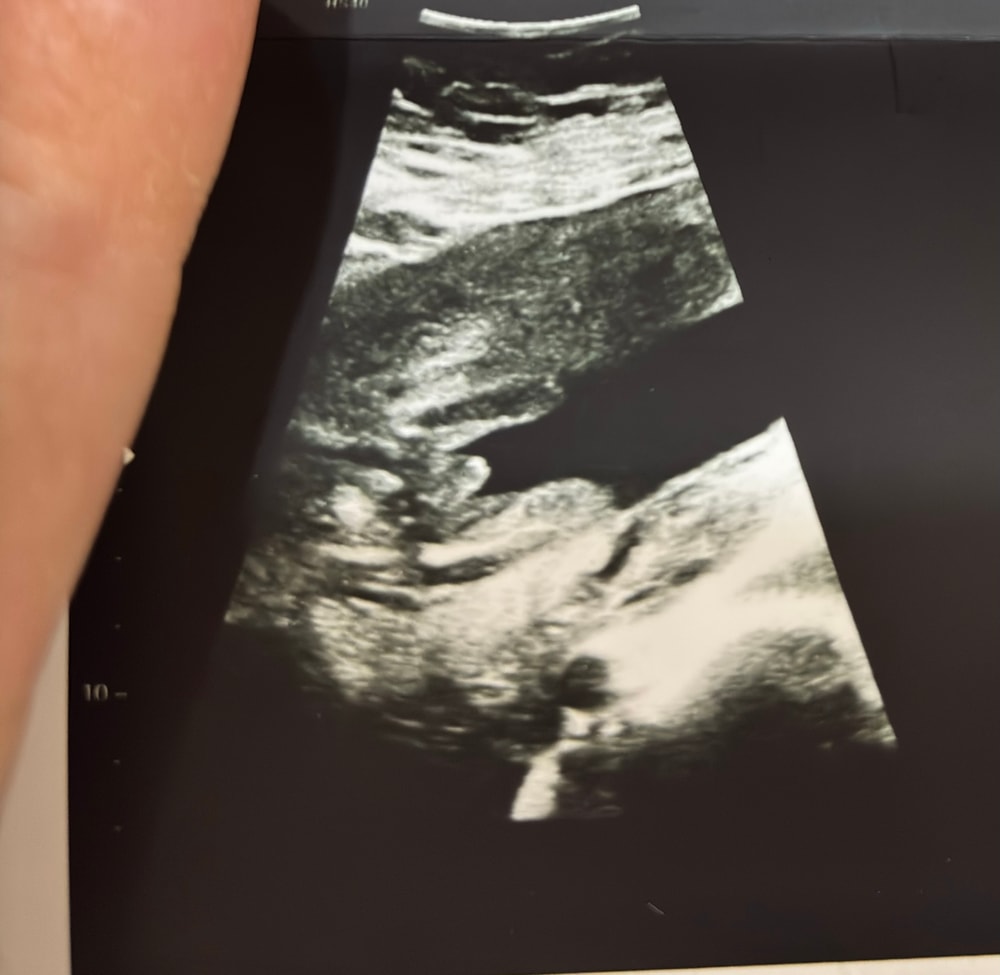

Анюта Долгополова,

примерно так и выглядит,только не такой пухлый на более раннем сроке😁

Левый нижний угол)